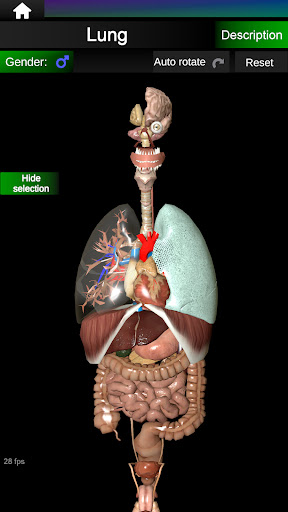

* Respiratory system, which includes the trachea, bronchi, lungs and an animation of this system.

* Easy to access and navigate (zoom, 3D rotation).

* Hide or show information.

* Compare male and female organs.